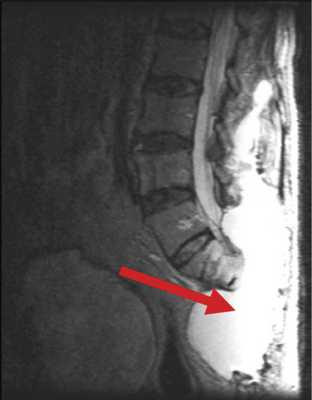

В случае пациента Б., 78 лет, после высокой ампутации крестца, в блок опухоли вошла часть m. erector spinae. Для пластики дефекта были использованы большие ягодичные мышцы, левый лоскут был частично развернут. У пациента наблюдался дефицит массы тела, развившийся на фоне выраженного болевого синдрома, который, в частности, сопровождал акт дефекации. В связи с этим пациент старался меньше есть, за счет чего масса тела снизилась с 86 до 65 кг за 1 мес. Нарушение репаративной функции привело к отсутствию сращения мягких тканей, сформировалась полость, заполненная серозной жидкостью, общим объемом около 5 л (рис. 3). Рис. 3. Гигантская серозная полость как осложнение сакрэктомии (указана стрелкой).

Для лечения подобных осложнений используется метод транспозиции ректоабдоминального лоскута в пресакральную область ректоабдоминальным доступом (рис. 4). Рис. 4. Пример использования метода транспозиции ректоабдоминального лоскута на питательной ножке. а — МРТ больного после операции, сагиттальная проекция. Перемещенный дедерматизированный ректоабдоминальный лоскут указан стрелкой; б — схематическое изображение перемещения лоскута.

Несмотря на продолженный рост и метастазирование опухоли (хондроид-хордома GIII), серозная полость регрессировала, рана зажила первичным натяжением в течение 10 сут.